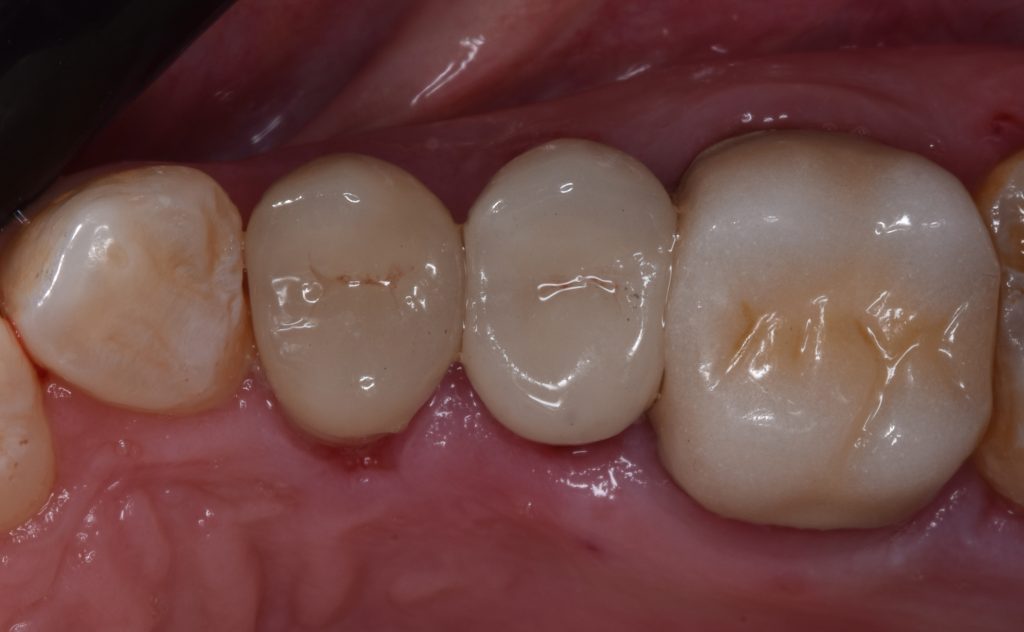

And final design to receive to monolithic lithium disilicate restorations

Cementation by heated composite

Shofu beautifill LS